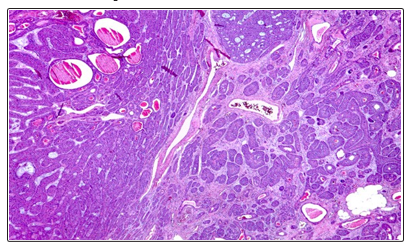

- Microscopic examination showed a benign tumor proliferation encapsulated compact architecture, in situ clusters and channels with eosinophilic content. The epithelial cells have a basaloid appearance bordered at the periphery by a palisade cell base. They are of small to medium size, provided with ovoid cores with fine chromatin. The cytoplasm is abundant basophilic. The myoepithelial cells are sometimes cuboid, sometimes fusiform. The nuclei are discreetly elongated hyperchromic. The cytoplasm is scarce eosinophilic (Figures 2, 3, 4). The massive elm form (3 cases) and the menbranous form (1 case)

Figure 3: Encapsulated Benign Tumor Proliferation Of Compact Architecture, In Situ Clusters And In Channels With Eosinophic Content

Figure 4: The epithelial cells have a basaloid appearance bordered at the periphery by a palisade cell base

The cells are small to medium in size, with ovoid nuclei of fine chromatin. The cytoplasm is abundant basophilic. The myoepithelial cells are sometimes cuboid, sometimes fusiform. The nuclei are discreetly elongated hyperchromic. Cytoplasm is scarce eosinophilic